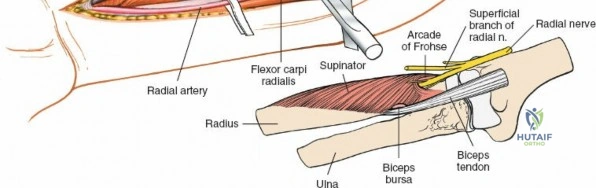

The Posterior Interosseous Nerve (PIN)

The posterior interosseous nerve is the single most important structure left vulnerable during exposure of the proximal radius. A branch of the radial nerve, the PIN dives into the supinator muscle through the Arcade of Frohse. It travels obliquely and spirally around the radial neck and proximal shaft within the substance of the supinator. In approximately 25% of patients, the nerve comes into direct contact with the posterior periosteum of the radial neck. Therefore, any blind placement of retractors around the posterior aspect of the proximal radius is strictly contraindicated, as it can easily crush the nerve against the bone, resulting in devastating loss of finger and thumb extension.

Exposing the proximal third of the radius requires extreme vigilance due to the proximity of the posterior interosseous nerve. The key anatomical landmark here is the insertion of the biceps tendon. Follow the biceps tendon distally to its insertion on the bicipital tuberosity of the radius. A small bursa lies just lateral to the tendon; incise this bursa to gain initial access to the proximal radial shaft. Because the radial artery lies superficial and medial to the tendon at this level, all deep dissection must remain strictly lateral to the biceps tendon.

The proximal radius is draped by the supinator muscle. The PIN passes directly through the belly of the supinator. To protect the nerve, the forearm must be fully supinated. Supination dynamically rotates the radius, carrying the insertion of the supinator anteriorly and simultaneously displacing the PIN laterally and posteriorly, safely away from the surgical field.

With the forearm fully supinated, identify the broad insertion of the supinator on the anterior aspect of the radius. Incise the supinator directly along the line of its insertion onto the bone. It is critical to detach the muscle by dividing its insertion sharply at the bone, rather than splitting the muscle belly, which would risk cutting the PIN.

Proceed with strict subperiosteal dissection, elevating the supinator laterally off the bone. This is one of the rare instances in orthopedic surgery where the safety gained by staying in a subperiosteal plane completely outweighs the theoretical vascular damage to the bone caused by periosteal stripping. The elevated supinator muscle belly now acts as a protective cushion for the PIN.